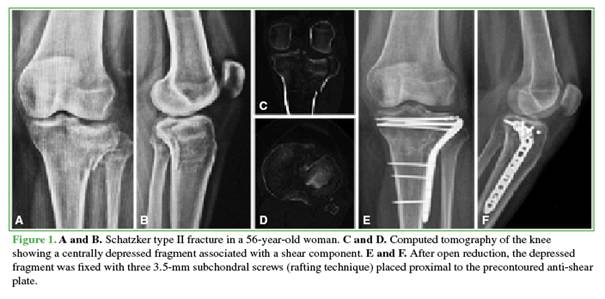

After reduction, preliminary fixation was performed with Kirschner wires. In the rafting technique group (Figure 1), definitive fixation was achieved with 3.5-mm subchondral screws placed through the plate when its design allowed adequate subchondral positioning. When this was not possible, the screws were placed proximally outside the plate.